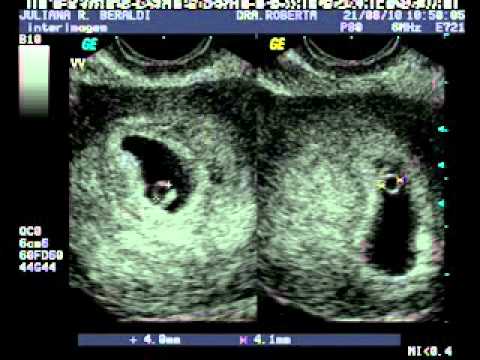

Na primeira ecografia gestacional a partir da 6º semana de gestação já é possível saber se a gravidez é de gêmeos. é a contretização do milagre da vida. Veja também a gestação do meu sobrinho.

Ainda é início da gestação e você pode até saber que está grávida mas a certeza que será uma gestação de gêmeos será somente lá pela 6ª semana quando você fizer sua primeira ecografia. Precisaria de fazer uma ecografia às 6 semanas para confirmar uma gravidez gémea. Porém não existe consenso quanto ao que seria ideal em termos do tipo e da frequência de exames de ultrassonografia para otimizar os desfechos.

Nesse mesmo exame geralmente se vemos dois sacos gestacionais distintos sabemos que serão gêmeos fraternos ou seja é mais provável que sejam de óvulos e espermatozoides diferentes. A partir de 6 semanas pode fazer mas não necessariamente vai dar pra ouvirver. Aqui está o que pode esperar na sua ecografia de 9 semanas. Como se sentiu às 6 semanas grávida de gémeos. Portanto repita seu exame entregando nas mãos do Deus Soberano. A sua barriga gémea às 6 semanas pode não parecer grande coisa por isso ir ao médico para uma ecografia é fundamental para saber se está realmente a ter gémeos. Na primeira ecografia gestacional a partir da 6º semana de gestação já é possível saber se a gravidez é de gêmeos. Se não se deixarem ver não pagará a sessão. Hora de ir ao médico O tamanho do embrião com 6 semanas de gestação é de 4 a 6 milímetros sendo equivalente ao tamanho de uma semente de romã.

A pequena cabeça do embrião apresenta duas manchas escuras que darão origem aos seus olhos e covinhas que formarão as orelhas e as narinas. A sua barriga gémea às 6 semanas pode não parecer grande coisa por isso ir ao médico para uma ecografia é fundamental para saber se está realmente a ter gémeos. Por esta altura o seu bebé já não será um embrião e será um fetoo batimento cardíaco de um feto também pode ser detectado numa ecografia de 9 semanas. Ver o coraçãozinho batendo é inexplicavel. Ainda é início da gestação e você pode até saber que está grávida mas a certeza que será uma gestação de gêmeos será somente lá pela 6ª semana quando você fizer sua primeira ecografia. Na primeira ecografia gestacional a partir da 6º semana de gestação já é possível saber se a gravidez é de gêmeos. é a contretização do milagre da vida.